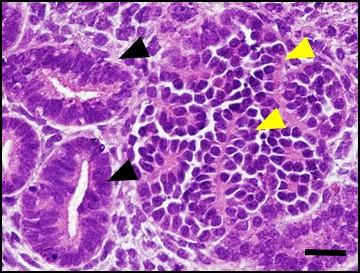

Research into kidney regeneration, an organ that has been extremely difficult to regenerate, has taken a great stride forward with research coming out of a collaboration between Kumamoto University, Japan and the National Cancer Institute (NCI) of the US. The research demonstrates a method of increasing kidney progenitor cell proliferation in vitro. These progenitor cells contribute to the formation of kidney tissues but normally disappear before or soon after birth. The research is the first in the world to establish methods for culturing kidney progenitor cells that maintain their ability to form the glomerulus, one of the most important elements of the kidney.

Although the kidney, which not only produces urine but also plays a role in blood pressure control, is an absolutely essential organ to sustain life, it cannot be regenerated once it has lost functionality. The glomeruli and tubules are the main functional components of the kidney. Glomeruli filter the blood to make urine, and both the glomeruli and the tubules are generated from kidney progenitor cells during fetal life. These cells, however, are lost before or soon after birth when kidney development is completed. This is one of the major reasons why the kidney cannot be regenerated.

The optimized culture allowed kidney progenitor cells to retain their functionality (the ability to produce glomeruli and tubules) and grow up to 1,800 times their original amount over 20 days. In vivo, these cells disappear in about 10 days, but researchers using this method are now able to retain them for twice that amount of time. Additionally, the increase in the total amount of cells is approximately 100 times the amount normally found inside the body.

Further testing of this culture method on kidney progenitor cells derived from human iPS cells resulted in four times the total amount of cells over 8 days. These cells also retained the potential to form glomeruli and tubules. This finding, a culture method that increases kidney progenitor cells while maintaining glomerulus-formation potential, is the first of its kind.